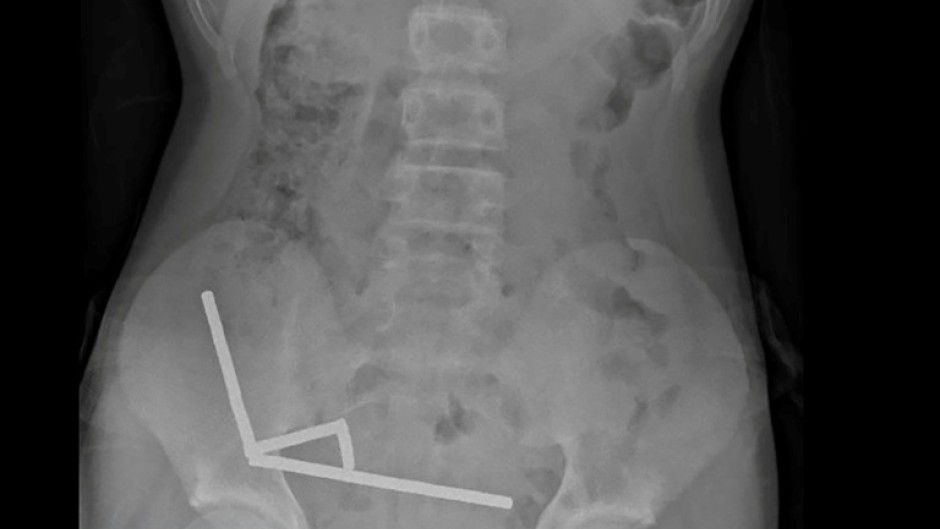

An X-ray showed the magnets had clumped together in four straight lines inside the child's intestines.

"These appeared to be in separate parts of bowel adhered together due to magnetic forces," they said.